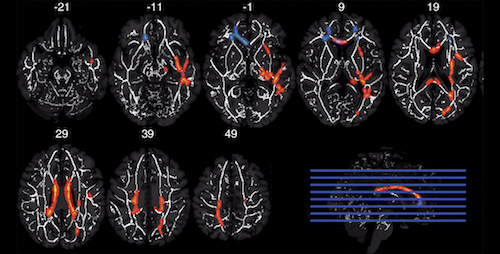

L'équipe de recherche a recruté 64 anciens joueurs de football américain des collèges ainsi que des professionnels, âgés de 52 à 65 ans. La moitié des anciens athlètes ont joué uniquement au collège et la moitié a continué dans la ligue professionnelle. La moitié des anciens joueurs ont signalé trois commotions cérébrales ou plus, tandis que l'autre moitié a signalé une ou aucune commotion cérébrale antérieure. Les chercheurs ont recruté un nombre égal de postes de jeu rapides et lents, ces derniers évoluant en ligne offensive ou défensive. L'imagerie du tenseur de diffusion (DTI) et l'IRM fonctionnelle (IRMf) ont été utilisées pour examiner 61 des anciens joueurs. Les données IRM des trois autres joueurs ont été exclues en raison d'un mouvement excessif ou de l'impossibilité de passer l'examen IRM. Le DTI a été utilisé pour analyser l'intégrité structurale de la substance blanche, tandis que l'IRMf était utilisée pour évaluer la fonction cérébrale pendant que les joueurs exécutaient une tâche de mémoire.

"Alors que le DTI et l'IRMf ont déjà été utilisés dans le domaine de la recherche sur les commotions, nous sommes parmi les premiers à combiner les deux techniques, a déclaré le co-auteur Michael Clark, étudiant en médecine à UNC-Chapel Hill. Nous nous sommes intéressés à la façon dont la matière blanche pourrait être affectée par l'exposition aux chocs de tête en fonction de la durée de carrière et de la position, cette exploration étant étendue à la capacité à recruter des ressources cérébrales pour accomplir une tâche de mémoire. En utilisant deux types différents et complémentaires d'IRM, nous avons pu voir la relation entre la structure et la fonction, qui sont toutes deux affectées par l'exposition aux chocs de tête. " Les résultats ont montré une interaction significative entre la durée de la carrière et l'historique de la commotion cérébrale. Les anciens joueurs d'université ayant fait l'objet de trois commotions cérébrales ou plus présentaient une intégrité inférieure, dans une zone de substance blanche largement remaniée, par rapport à ceux ayant subi une commotion cérébrale ou moins. Cependant, le contraire était vrai pour les anciens joueurs professionnels.

Les chercheurs pensent que les joueurs qui ont une longue carrière, qui sont exposés à des événements commotionnels récurrents et qui sont cognitivement normaux à la fin de la cinquantaine, ne sont peut-être pas représentatifs de l'ensemble des anciens joueurs de football professionnels. "Nous ne savons pas exactement pourquoi c'est le cas pour les anciens pros, remarque Michael Clark. Cela peut avoir à voir avec l'échantillon d'athlètes que nous avons recrutés dans l'étude. Mais les résultats pourraient suggérer qu'une carrière avec une exposition supplémentaire au football n'est pas nécessairement pire qu'une durée d'exposition plus courte." D'autre part, les joueurs lents sujets aux commotions cérébrales récurrentes ont montré une intégrité réduite de la substance blanche frontale et une plus faible mesure d'activation, pendant la tâche de mémoire, à l'IRMf que ceux ayant subi une commotion cérébrale ou moins. Ce n'était pas le cas pour les joueurs rapides.

Les interactions observées entre les antécédents de commotion cérébrale et les positions de jeu suggèrent qu'il peut y avoir des différences importantes dans les mécanismes de blessure entre les joueurs rapides et les autres joueurs. L'ampleur, l'emplacement et la fréquence des chocs de tête dans le football américain diffèrent selon le poste du joueur. Les "offensive backs" subissent des impacts à grande vitesse. Les "linemen", cependant, font l'objet d'impacts plus fréquents et ont la plus grande proportion de chocs sur l'avant du casque. La forte proportion de chocs frontaux subis par les joueurs lents peut entraîner des lésions plus localisées sur les surfaces frontales de la substance blanche comparée aux joueurs rapides, aux zones d'impact plus variables.